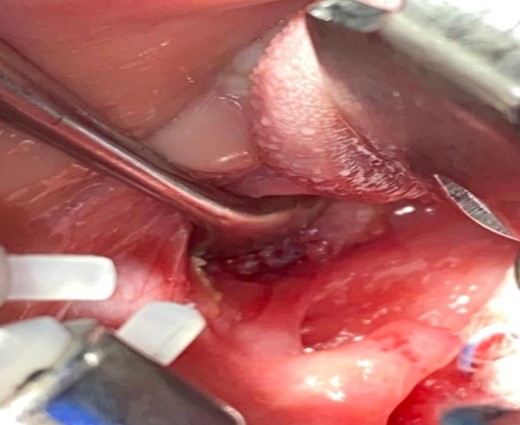

After draping and sterilisation, the small left-sided neck punctum was identified, probing of the fistula tract by a lacrimal probe was done, followed by the insertion of an arterial catheter inside the fistula tract (Fig. 6). The amount of methylene blue added was 0.01 ml per 2 ml of fibrin glue, and a total of 4 ml of this mixture was injected. This mixture allows the glue to be dyed adequately and does not inhibit its solidification. The arterial catheter was totally inserted, about 7 cm in length, and injection of methylene blue with fibrin glue was performed using an arterial catheter inside the tract. An elliptical incision was made around the fistula opening, followed by dissection of the tract. The tract was obvious, firm and colored with methylene blue. The tract was easily dissected without the need to remove extra tissues around it. Another superior incision, a step ladder incision, was made as the tract was long. The tract followed to its entry into the tonsillar fossa, which was ligated. The internal carotid artery, internal jugular vein, hypoglossal nerve and glossopharyngeal nerve were all identified and preserved. Bilateral tonsillectomy was performed, and the tract was visualised within the left tonsil (Figs 1–4). The left tract at the tonsillar bed after the tonsillectomy was ligated and cauterised. Then bilateral auricular sinus excision is done. The patient was then seen after 3 months of surgery and was doing well.

The branchial firm colored tract seen clearly after delivery it by upper step ladder incision. Notice the tract removed without excessive tissue removal around it.